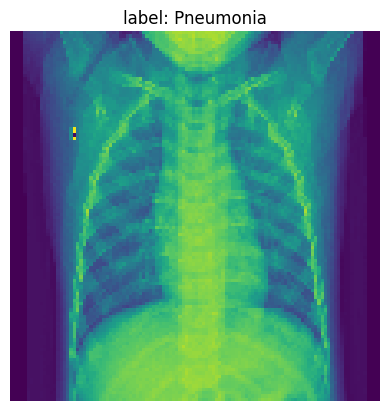

Pick one example from our training data to visualize our NN model’s learning after each layer. Below we print the original image.

img_idx= 36

img_tensor = x_test_t[img_idx].unsqueeze(0).cpu()

plt.imshow(img_tensor[0]);

plt.title(f'label: {full_label(str(y_test_t[img_idx]))}')

plt.axis('off')

plt.show()

../_images/023d7d71ebf59f4f897579184bb468bb01f37d3b68808cf8071621cca6ae265b.png

Now, let’s get some understanding of what the model looks when it is pneumonia

target_layers = [model_cnn.conv4]

input_tensor = x_test_t[200:232].unsqueeze(1)

targets = None

with HiResCAM(model=model_cnn, target_layers=target_layers) as cam:

cam.batch_size = 1

grayscale_cam = cam(input_tensor=input_tensor, targets=targets)

grayscale_cam = grayscale_cam[0, :]

img = x_val_t[251].cpu().numpy()

visualization = show_cam_on_image(np.stack((img, img, img), axis=-1), grayscale_cam, use_rgb=True)

plt.figure(figsize=(8,4))

plt.imshow(visualization)

plt.title(f"What makes the CNN model think that it is pneumonia?")

../_images/3aba00209ae2c78b70dfb6c7071e1fc18c5ac9516c13398ccd2cee58b7118e27.png